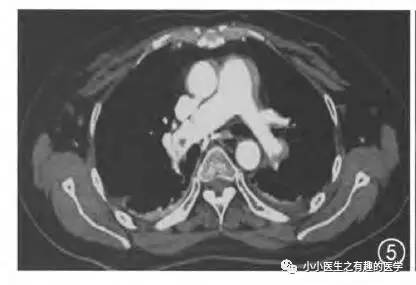

看看下图,这才是正常的肺动脉。

亲们,我说的不无道理吧?!

再复习一下,肺动脉乃人字形。